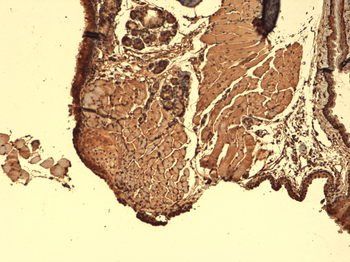

IHC-P staining of human thyroid tumour tissue using NIS antibody (2.5 ug/ml)